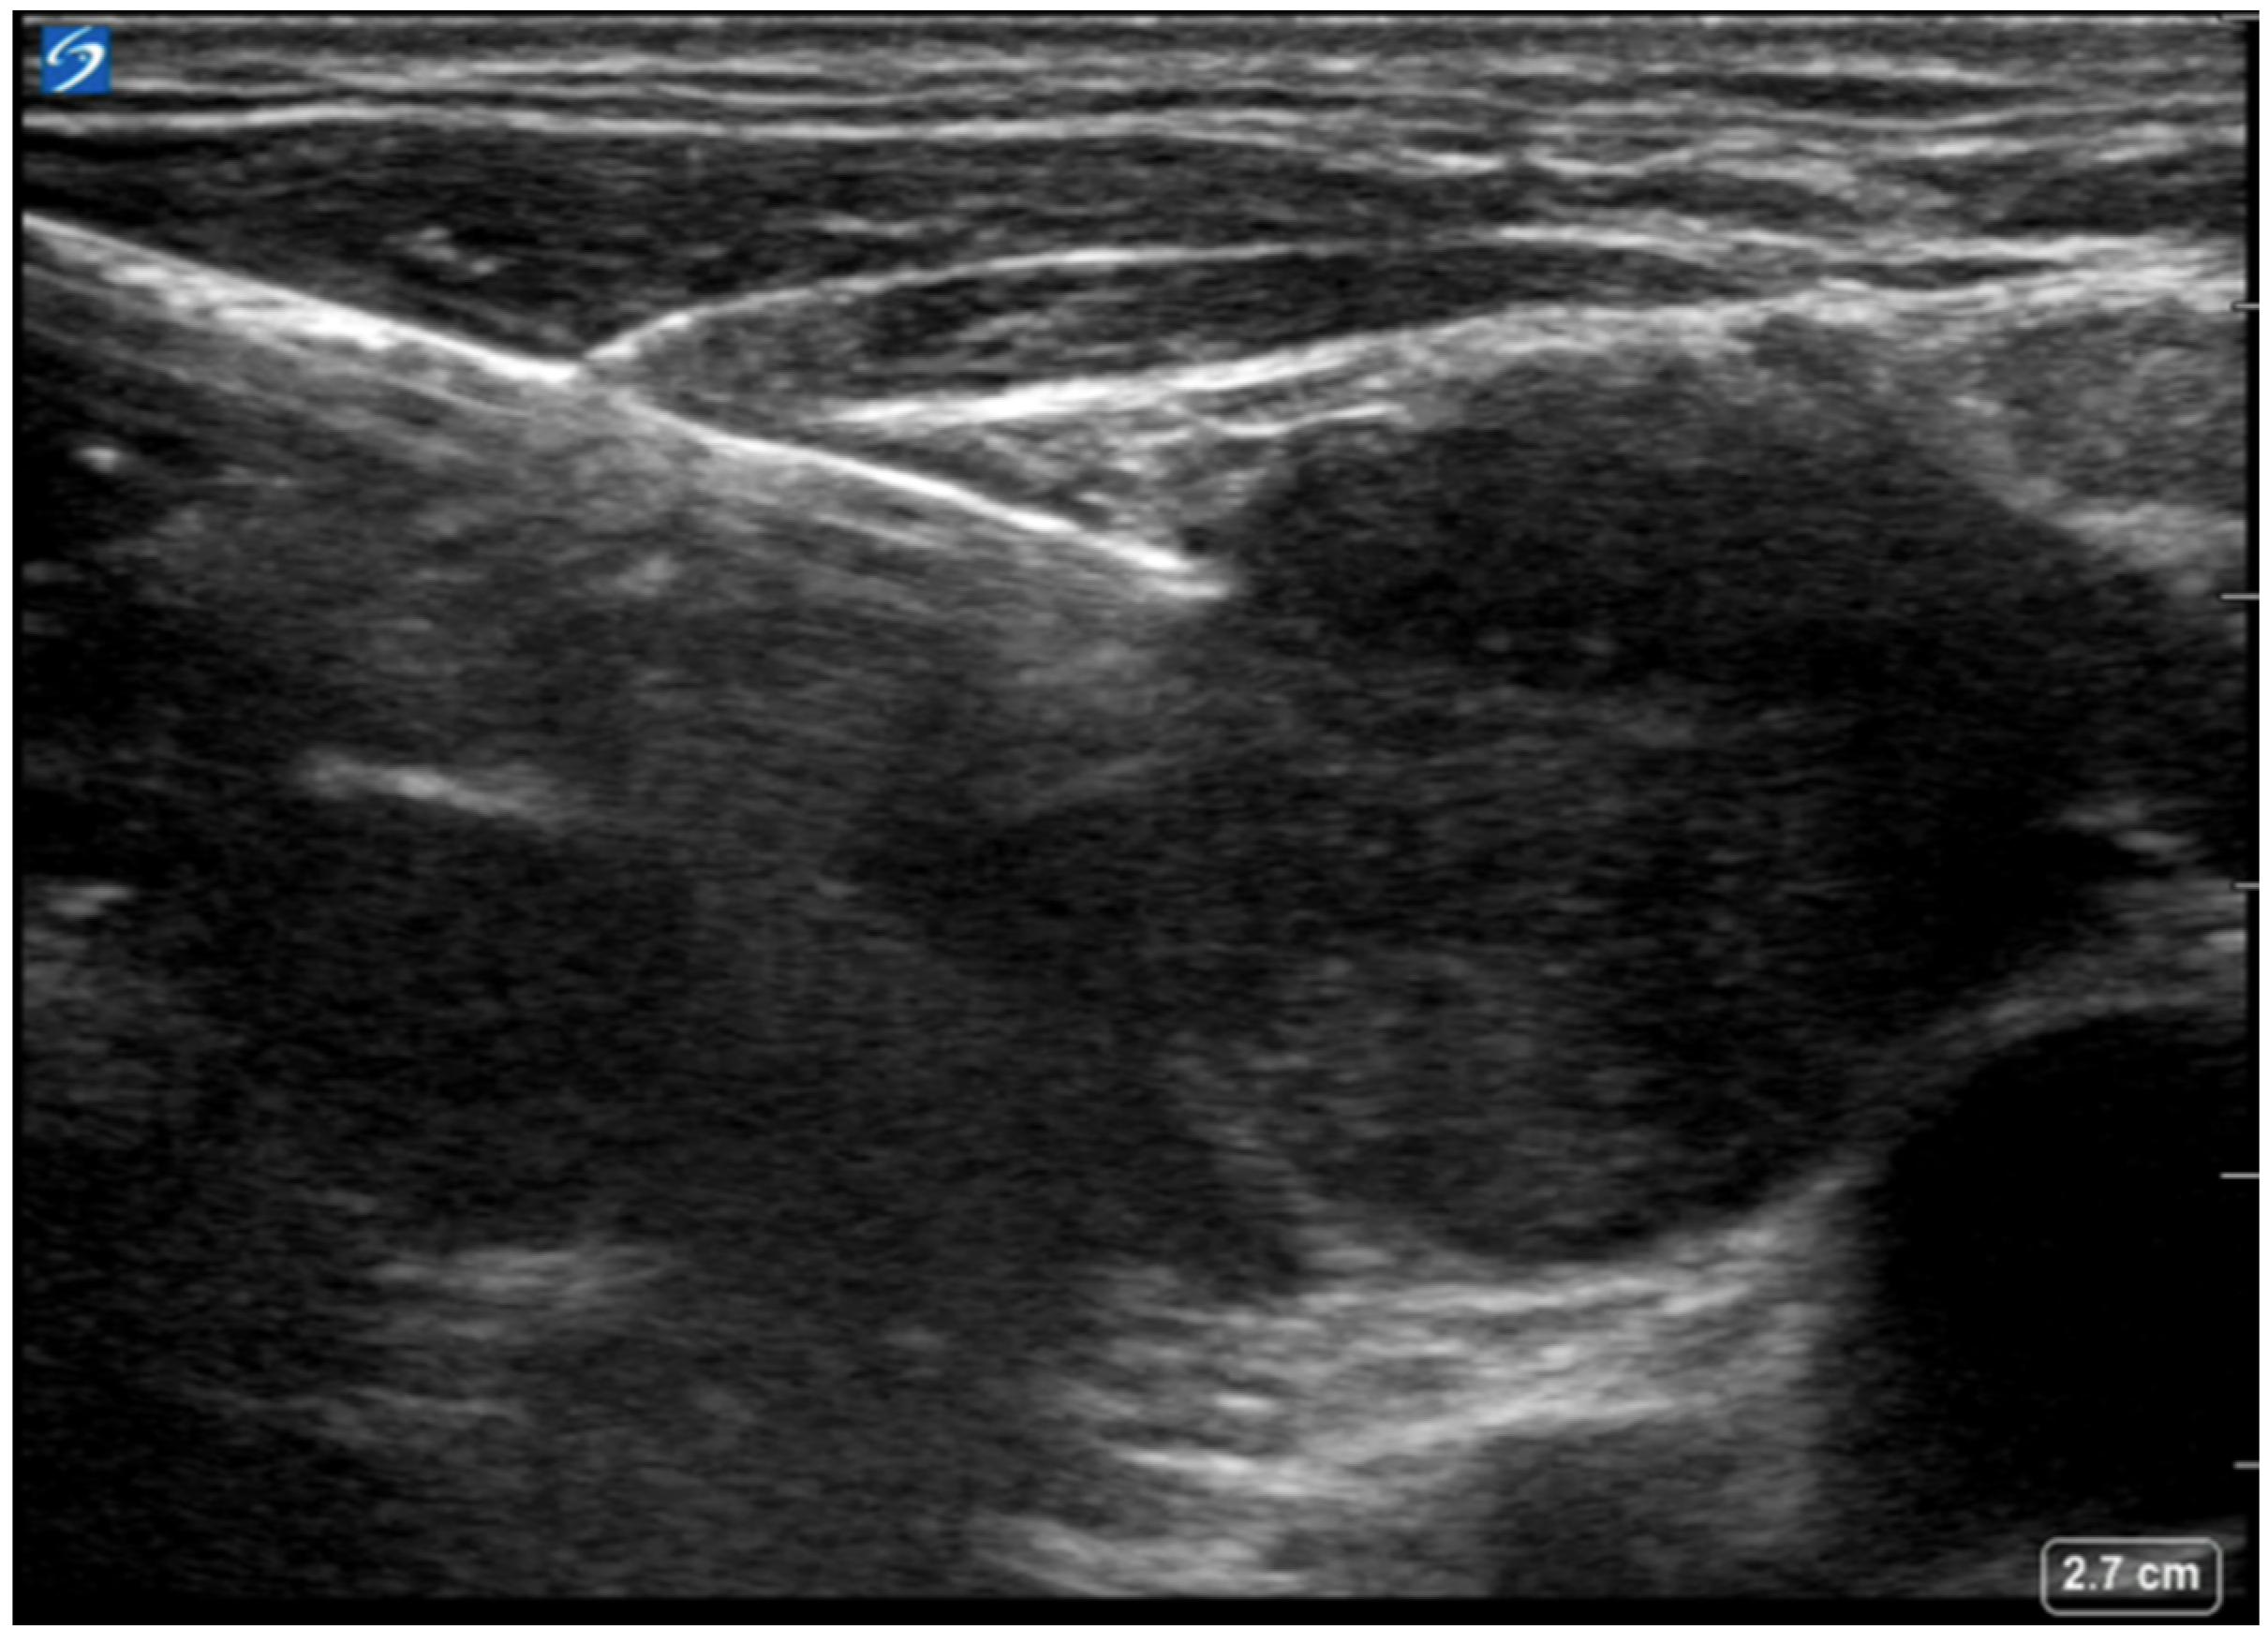

- Kumaran, M.; Benamore, R.E.; Vaidhyanath, R.; Muller, S.; Richards, C.J.; Peake, M.D.; Entwisle, J.J. Ultrasound guided cytological aspiration of supraclavicular lymph nodes in patients with suspected lung cancer. Thorax 2005, 60, 229–233. [Google Scholar] [CrossRef][Green Version]

- Takashima, S.; Sone, S.; Nomura, N.; Tomiyama, N.; Kobayashi, T.; Nakamura, H. Nonpalpable lymph nodes of the neck: Assessment with US and US-guided fine-needle aspiration biopsy. J. Clin. Ultrasound 1997, 25, 283–292. [Google Scholar] [CrossRef]

- Fultz, P.J.; Feins, R.H.; Strang, J.G.; Wandtke, J.C.; Johnstone, D.W.; Watson, T.J.; Gottlieb, R.H.; Voci, S.L.; Rubens, D.J. Detection and diagnosis of nonpalpable supraclavicular lymph nodes in lung cancer at CT and US. Radiology 2002, 222, 245–251. [Google Scholar] [CrossRef]

- van Overhagen, H.; Brakel, K.; Heijenbrok, M.W.; van Kasteren, J.H.L.M.; van de Moosdijk, C.N.F.; Roldaan, A.C.; van Gils, A.P.; Hansen, B.E. Metastases in supraclavicular lymph nodes in lung cancer: Assessment with palpation, US, and CT. Radiology 2004, 232, 75–80. [Google Scholar] [CrossRef]

- Ahmed, M.; Daneshvar, C.; Breen, D. Ultrasound-Guided Cervical Lymph Node Sampling Performed by Respiratory Physicians. Biomed. Hub. 2019, 4, 1–6. [Google Scholar] [CrossRef]